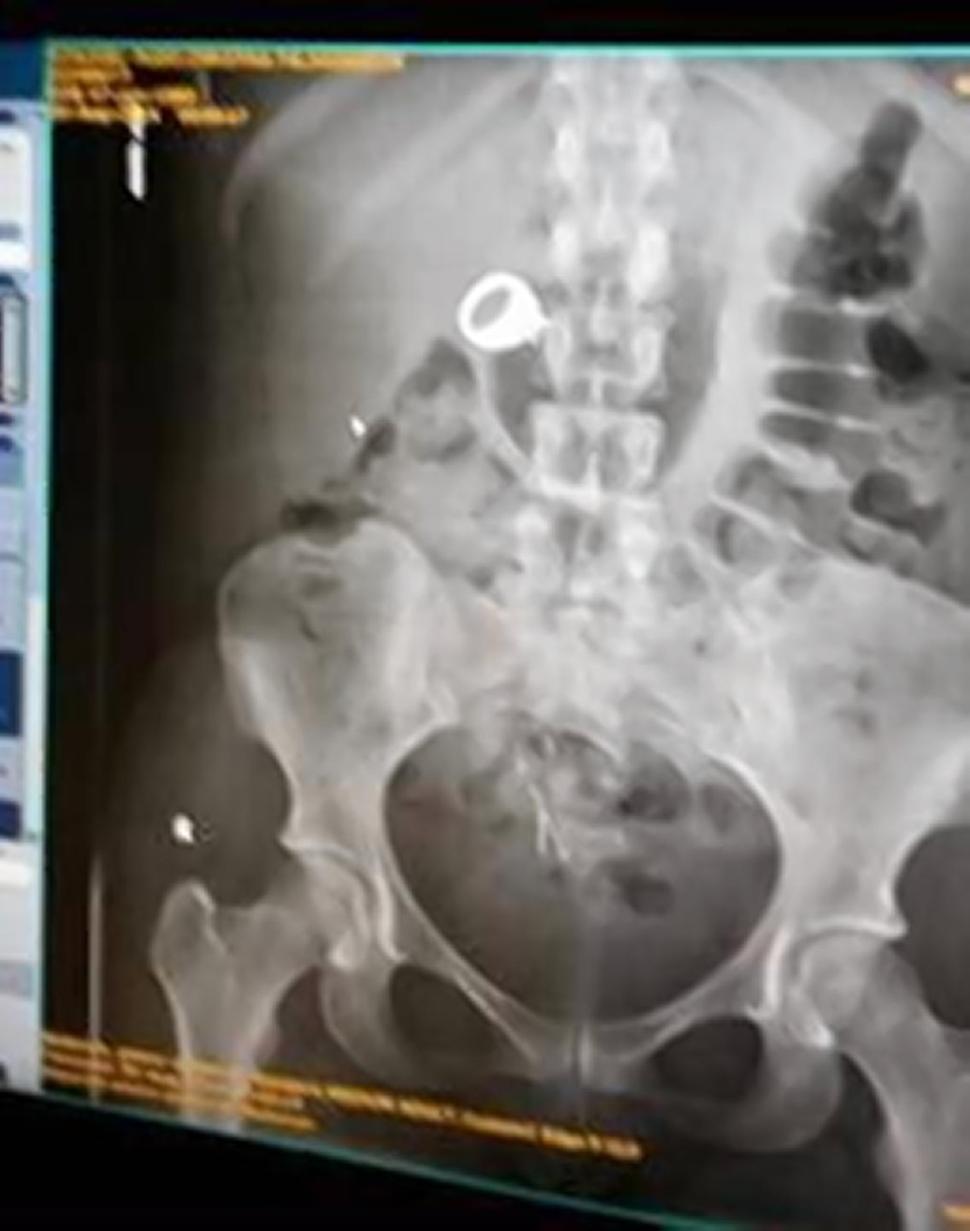

Christina Schlegel, 25 anni, e Bryan Ford, 30 anni, sono stati arrestati dopo avrebbe rubato un anello di nozze in un negozio Zales che si trova all’interno di un centro commerciale dello Utah. La polizia ha visto Ford scappare con l’anello: l’uomo è però riuscito a saltare nell’auto guidata dalla fidanzata e i due sono scappati via. La loro auto è stata fermata a breve distanza e l’anello non è stato trovato: una radiografia dello stomaco della donna ha però incastrato la ragazza, mostrando che lo aveva ingoiato.